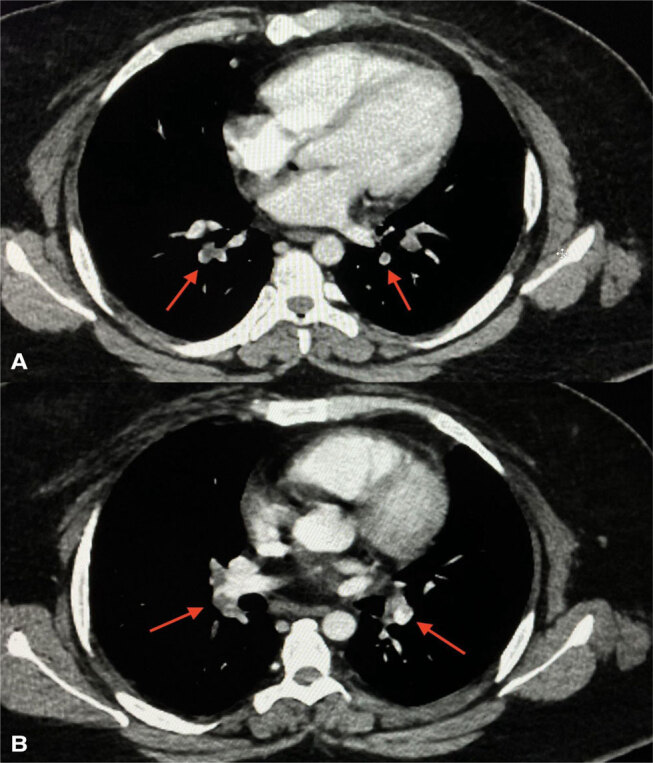

Abstract Image